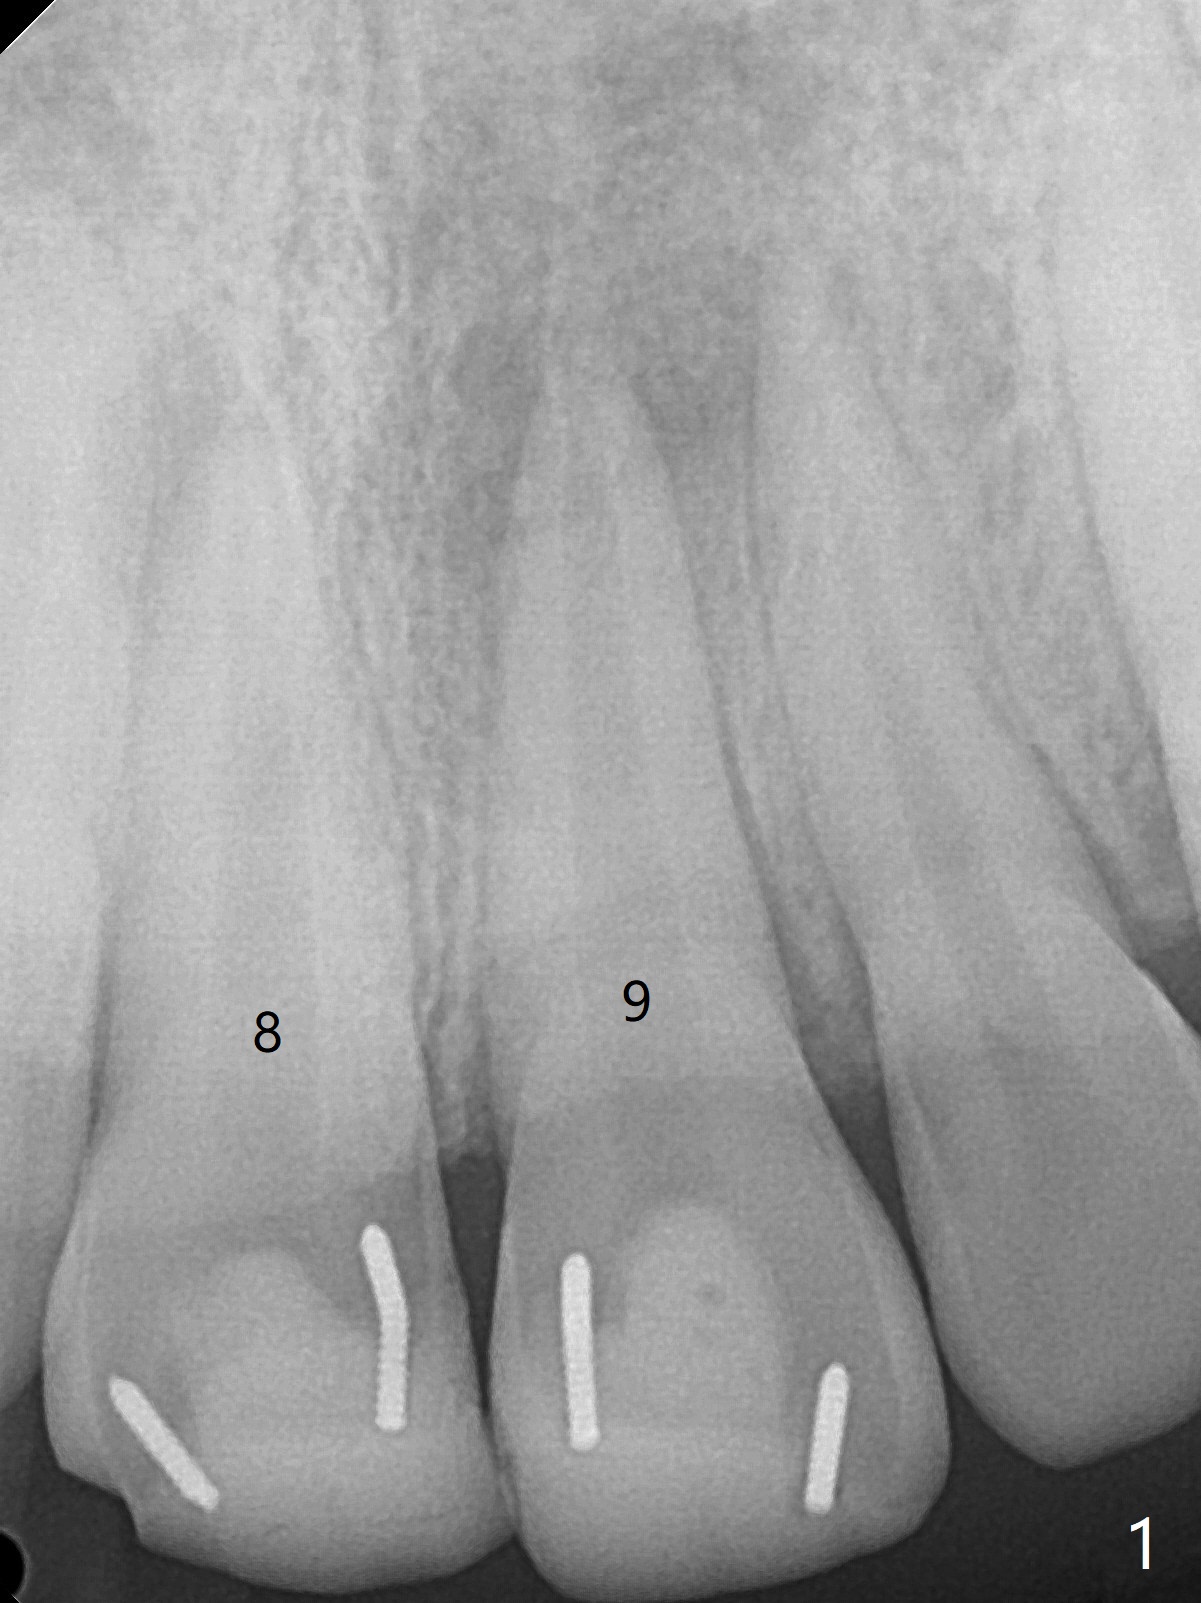

15岁男去年急诊来诊所左上1疼痛(图一:9号牙),两个中切牙8-9岁外伤,侧切牙活性测定:活髓,建议8,9 apexification。一年后(这个月)他又回来要求9号牙树脂修复(图二:*),他在马来西亚看望爸爸时,突然牙痛在那里做根管治疗。现在两个中切牙颊侧根尖都有触痛。树脂修补后,他回来做8号牙牙髓治疗,想象根管宽大,但是根尖2-3毫米根管弯曲,必须事先弯曲10号扩大针才能进入,最后扩大针是rotary file, 40/.04, 21.5毫米(图三),好像工作长度不够,仅仅增加半个毫米,使用15号扩大针,病人觉得疼痛(没用局麻药),不再扩大,保持原来根尖狭窄(可以吗?)。反复冲洗后放置氢氧化钙糊剂(图四),根管仿佛挺粗的,根尖根管还需要扩大吗?根尖片清晰度不好,看不出根尖闭锁与否,需要拍摄CT吗?需要使用MTA促进根尖关闭吗?